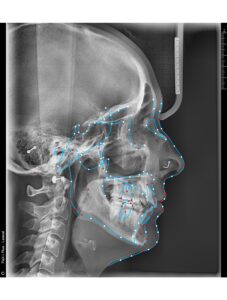

A 34- year old Caucasian female presents with a chief concern of “I don’t like my overbite and spaces between my front teeth.”